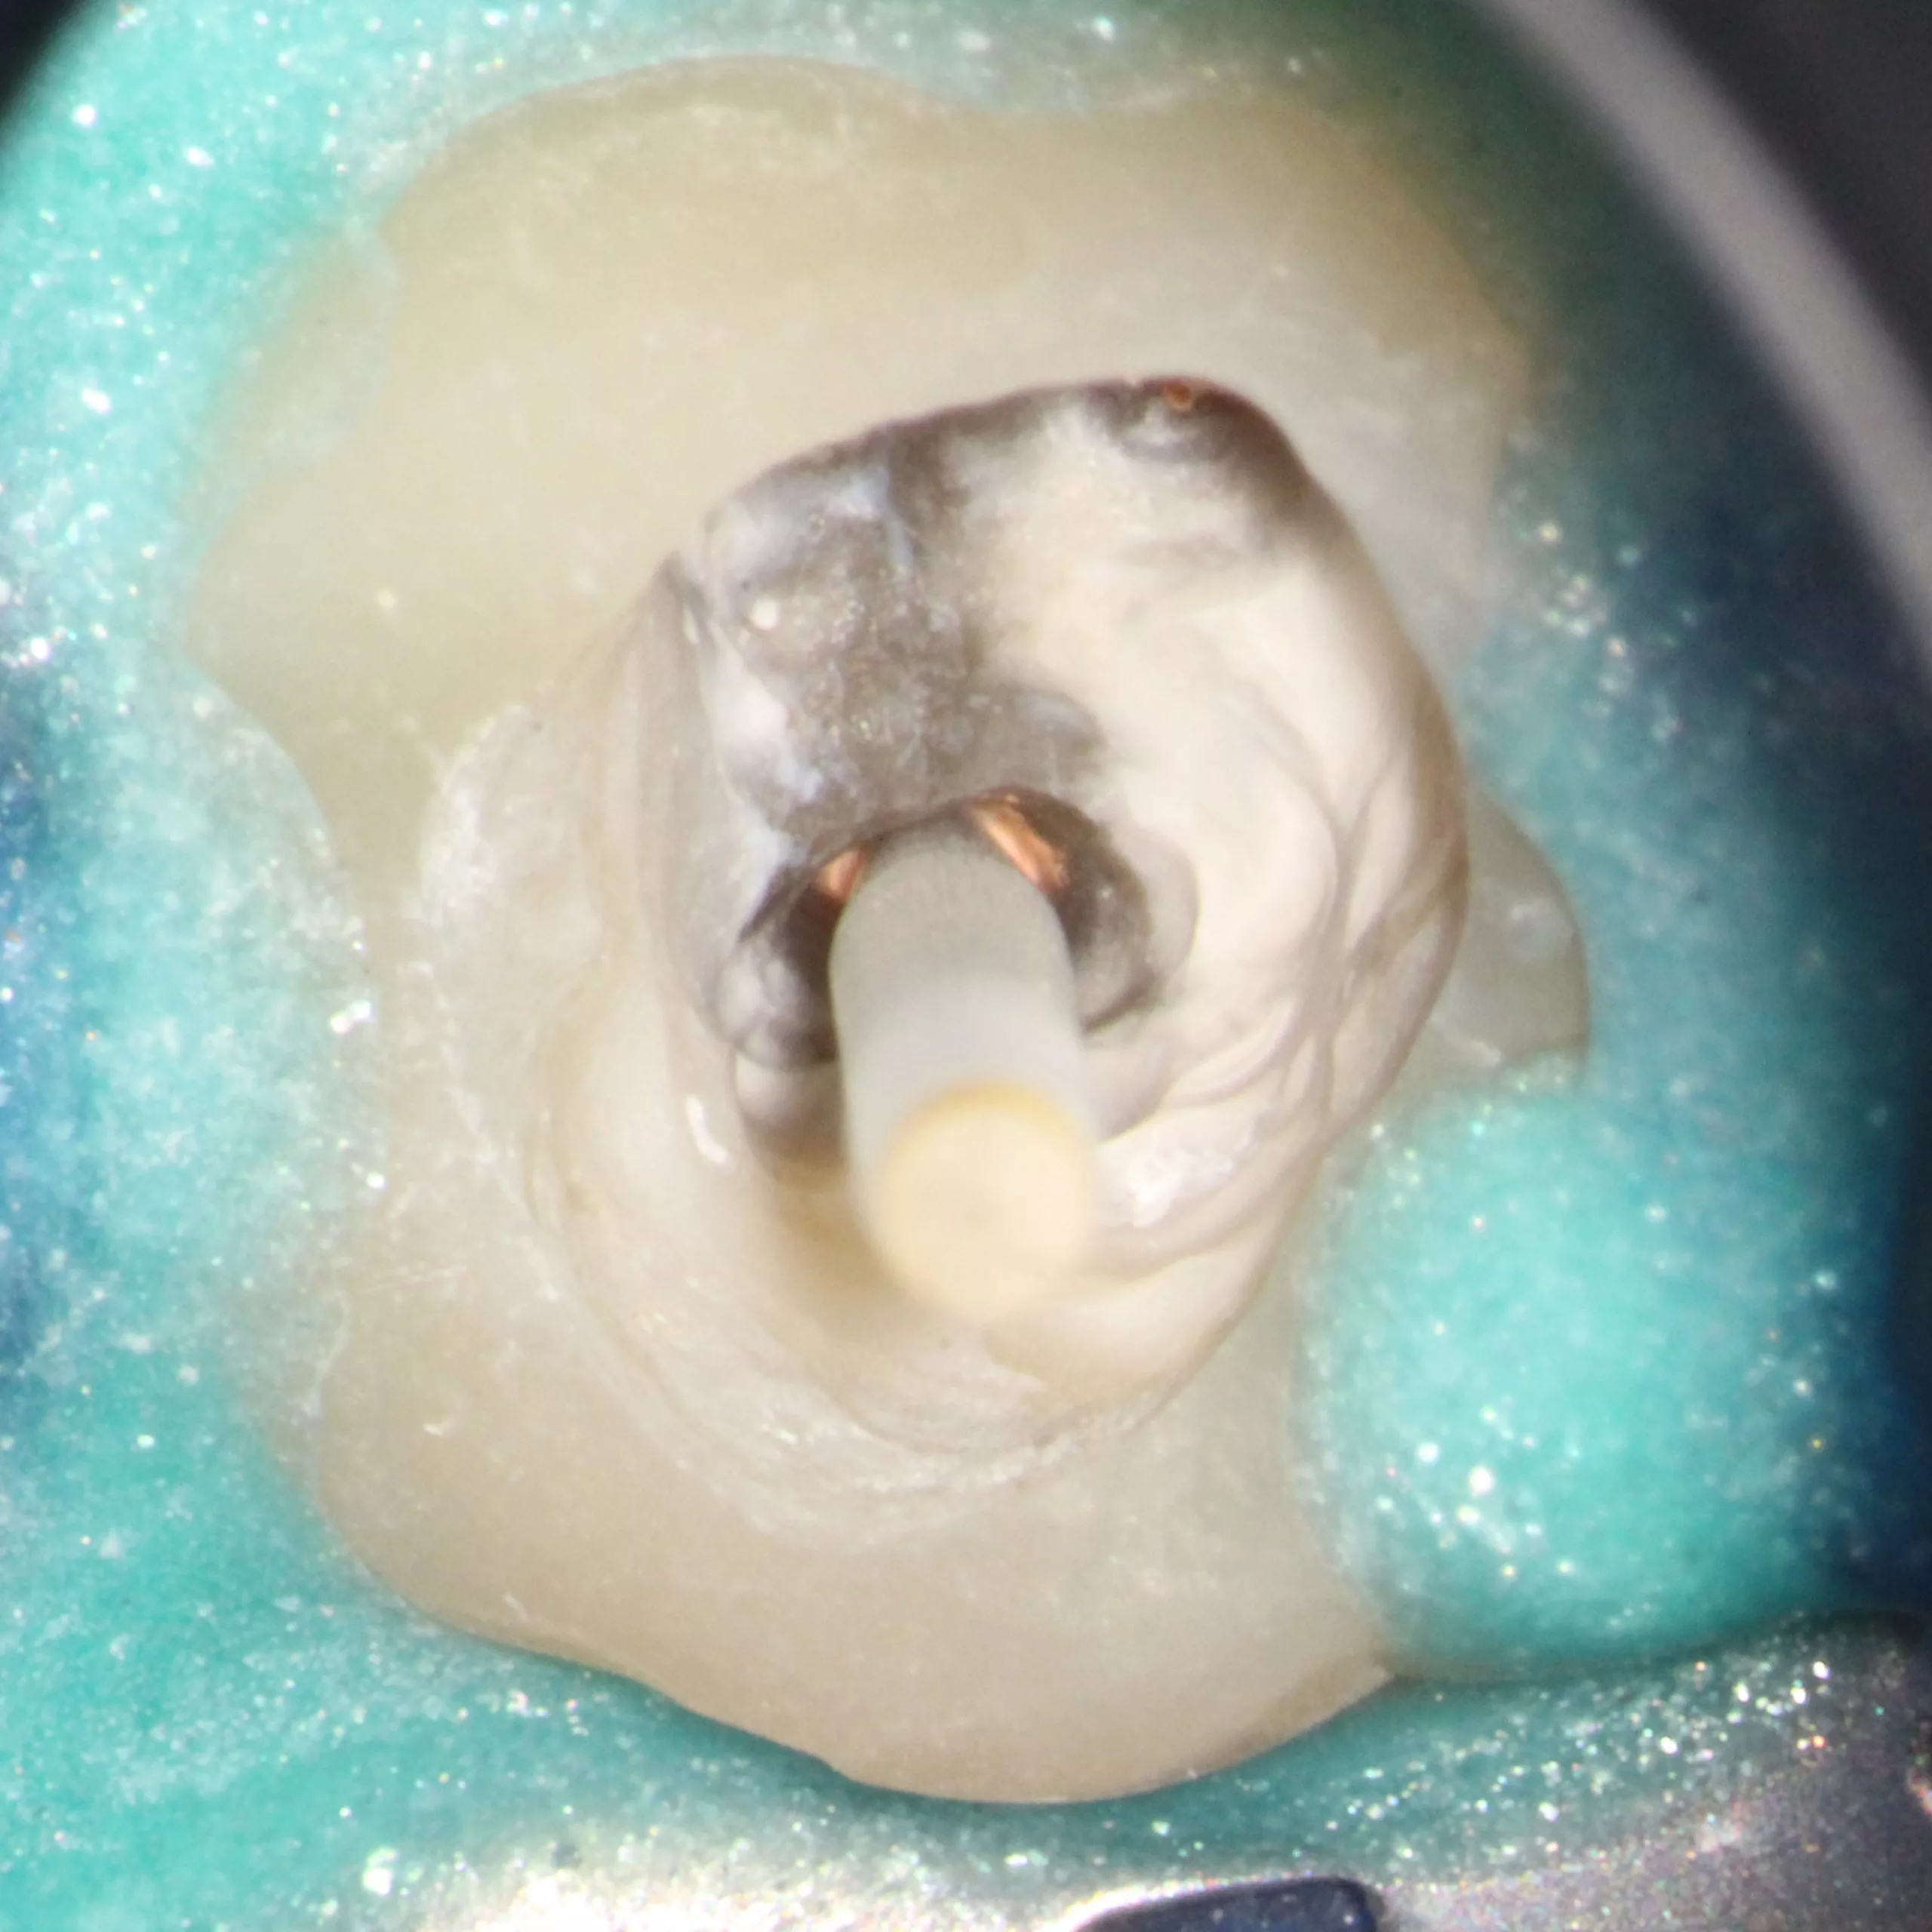

Die Abbildung 56 zeigt die Einprobe eines Glasfaserstiftes (EasyPost, Dentsply Sirona). Nach Vorbehandlung des Stiftes mit dem Visalys Restorative Primer und nach Reinigung des Kanalsystems mit AH Cleanser (Dentsply Sirona) sowie der Applikation des Visalys Tooth Primers im Zahn erfolgte die zeitgleiche Verklebung des Glasfaserstiftes mit Visalys CemCore (diesmal in der opaken Variante) und dem internen Aufbau des gesamten Zahnes. Die Abbildungen 57 bis 59 zeigen das 2-schichtige Einbringen von Visalys CemCore Opaque nach einer Zwischenhärtung des 1. Inkrements für 40 Sek., die Abbildung 60 die Röntgenkontrolle der Wurzelfüllung und des Stumpfaufbaus. Der okklusale Anteil der Kavität wurde wenige Minuten später von einem Kollegen okklusal reduziert und mit einem klassischen lichthärtenden Komposit definitiv versorgt.